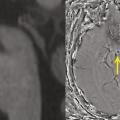

Amnésies transitoires

Les amnésies transitoires occupent une place particulière dans le domaine des troubles de la mémoire. L’ictus amnésique (IA) en est le prototype,1 mais les amnésies épileptiques, vasculaires, toxiques ou traumatiques doivent aussi être prises en considération.